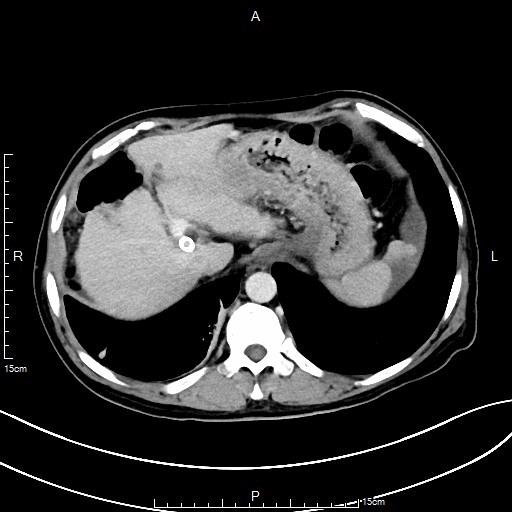

中年男性,肝硬化合并脾功能亢进。CT检查示巨脾,血常规检查示重度贫血及重度血小板减少症,应用PVA颗粒行部分性脾栓塞。

- DSA下行部分性脾动脉栓塞治疗。